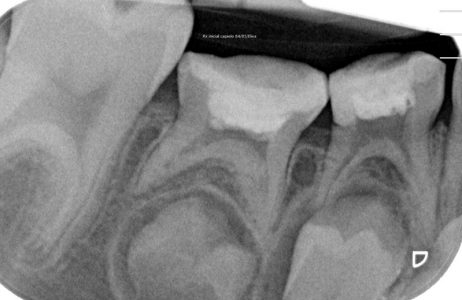

NUESTROS CASOS:

Endodoncia

Capielo